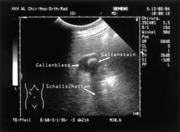

Sonografische Darstellung einer Gallenblase, mit pathologischem Befund (Gallenstein)

Zur Beurteilung der Gallenblase und der Gallenwege sowie eventueller krankhafter Erscheinungen steht eine Vielzahl von Untersuchungsmöglichkeiten zur Verfügung, von denen die Sonografie die verbreitetste ist.